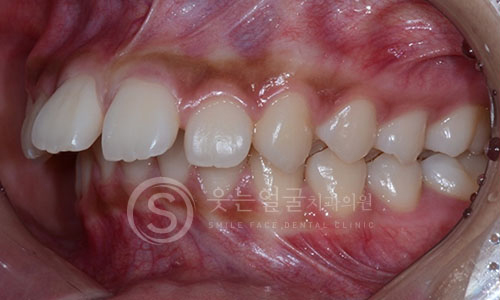

09 구내 촬영

한눈에 보는

치아교정 전후사진